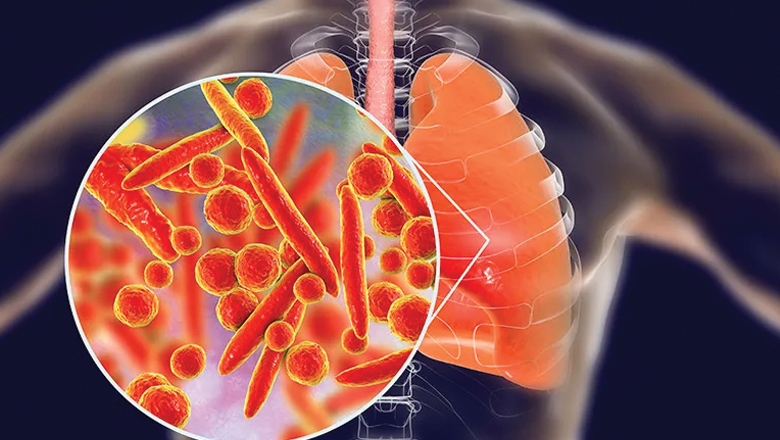

ഗുരുതര ശ്വാസകോശ അണുബാധയായ ന്യുമോണിയ വിവിധ രോഗകാരികള് മൂലമാണ് ഉണ്ടാകുന്നത്.

- · ബാക്ടീരിയ: സ്ട്രെപ്റ്റോകോക്കസ് ന്യുമോണിയയാണ് ഏറ്റവും സാധാരണമായ കാരണം.

- · വൈറസ്: RSV, ഇന്ഫ്ളുവന്സ, കൊറോണ വൈറസുകള്.

- · ഫംഗസ്: പ്രതിരോധശേഷി കുറഞ്ഞ വ്യക്തികളെ ബാധിക്കുന്നു.